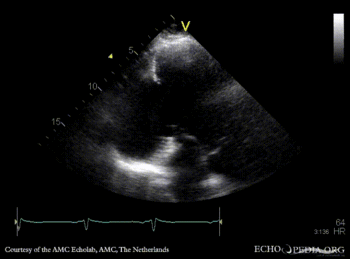

Large pseudoaneurysm of posterior wall

A2CH: large pseudoaneurysm of posterior wall, spontaneous echocontrast